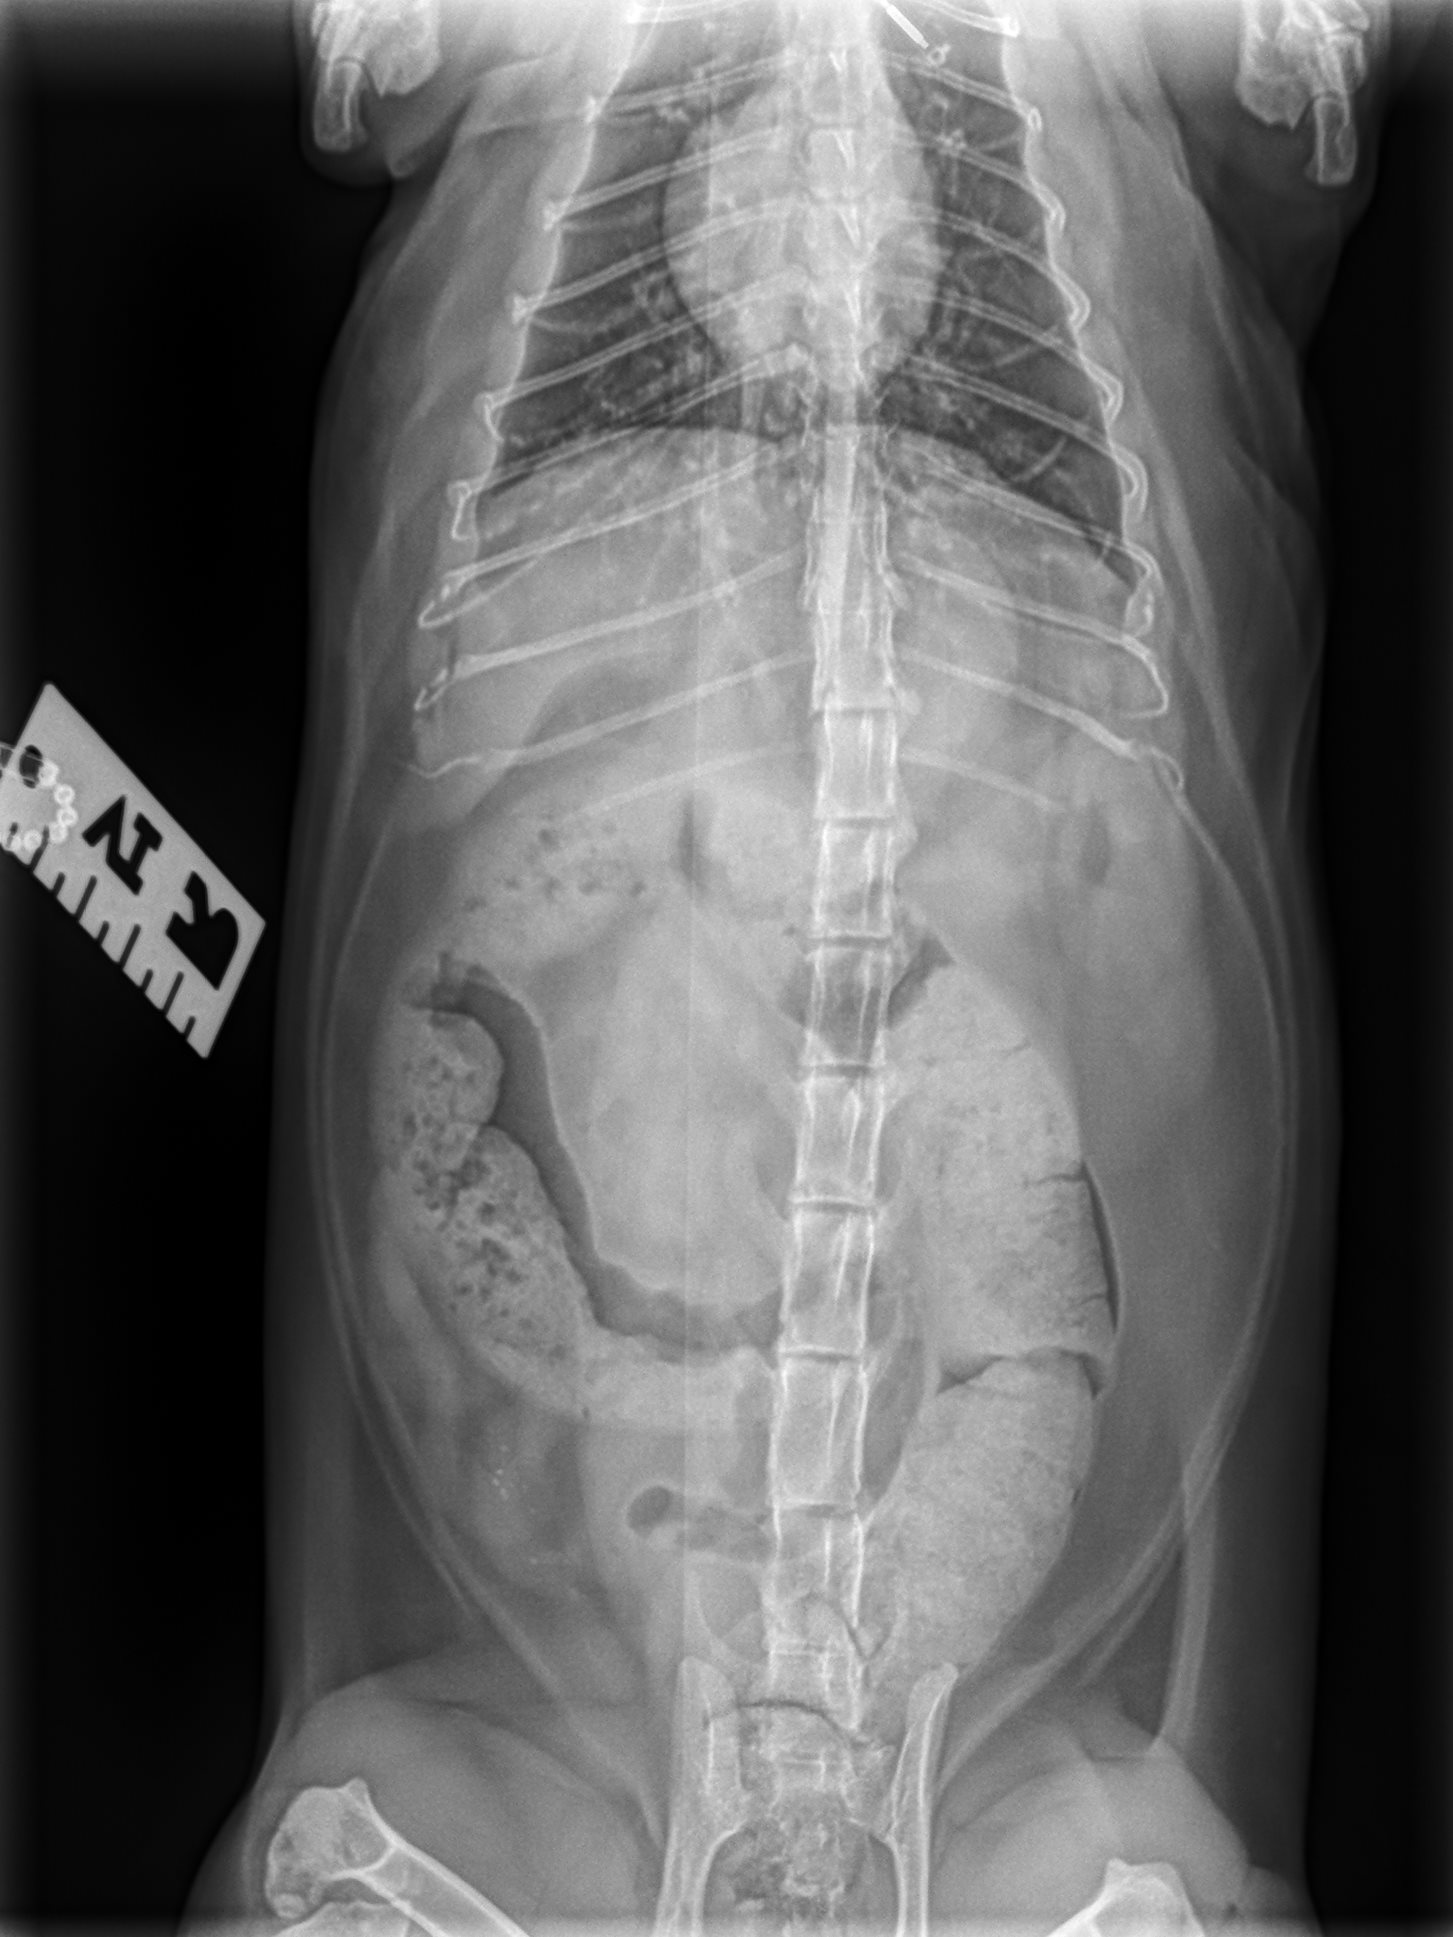

Next, your veterinarian will recommend X-rays to evaluate the extent of constipation to determine the best initial treatment for your cat. Bloodwork is often required to assess underlying diseases that may predispose your cat to constipation.